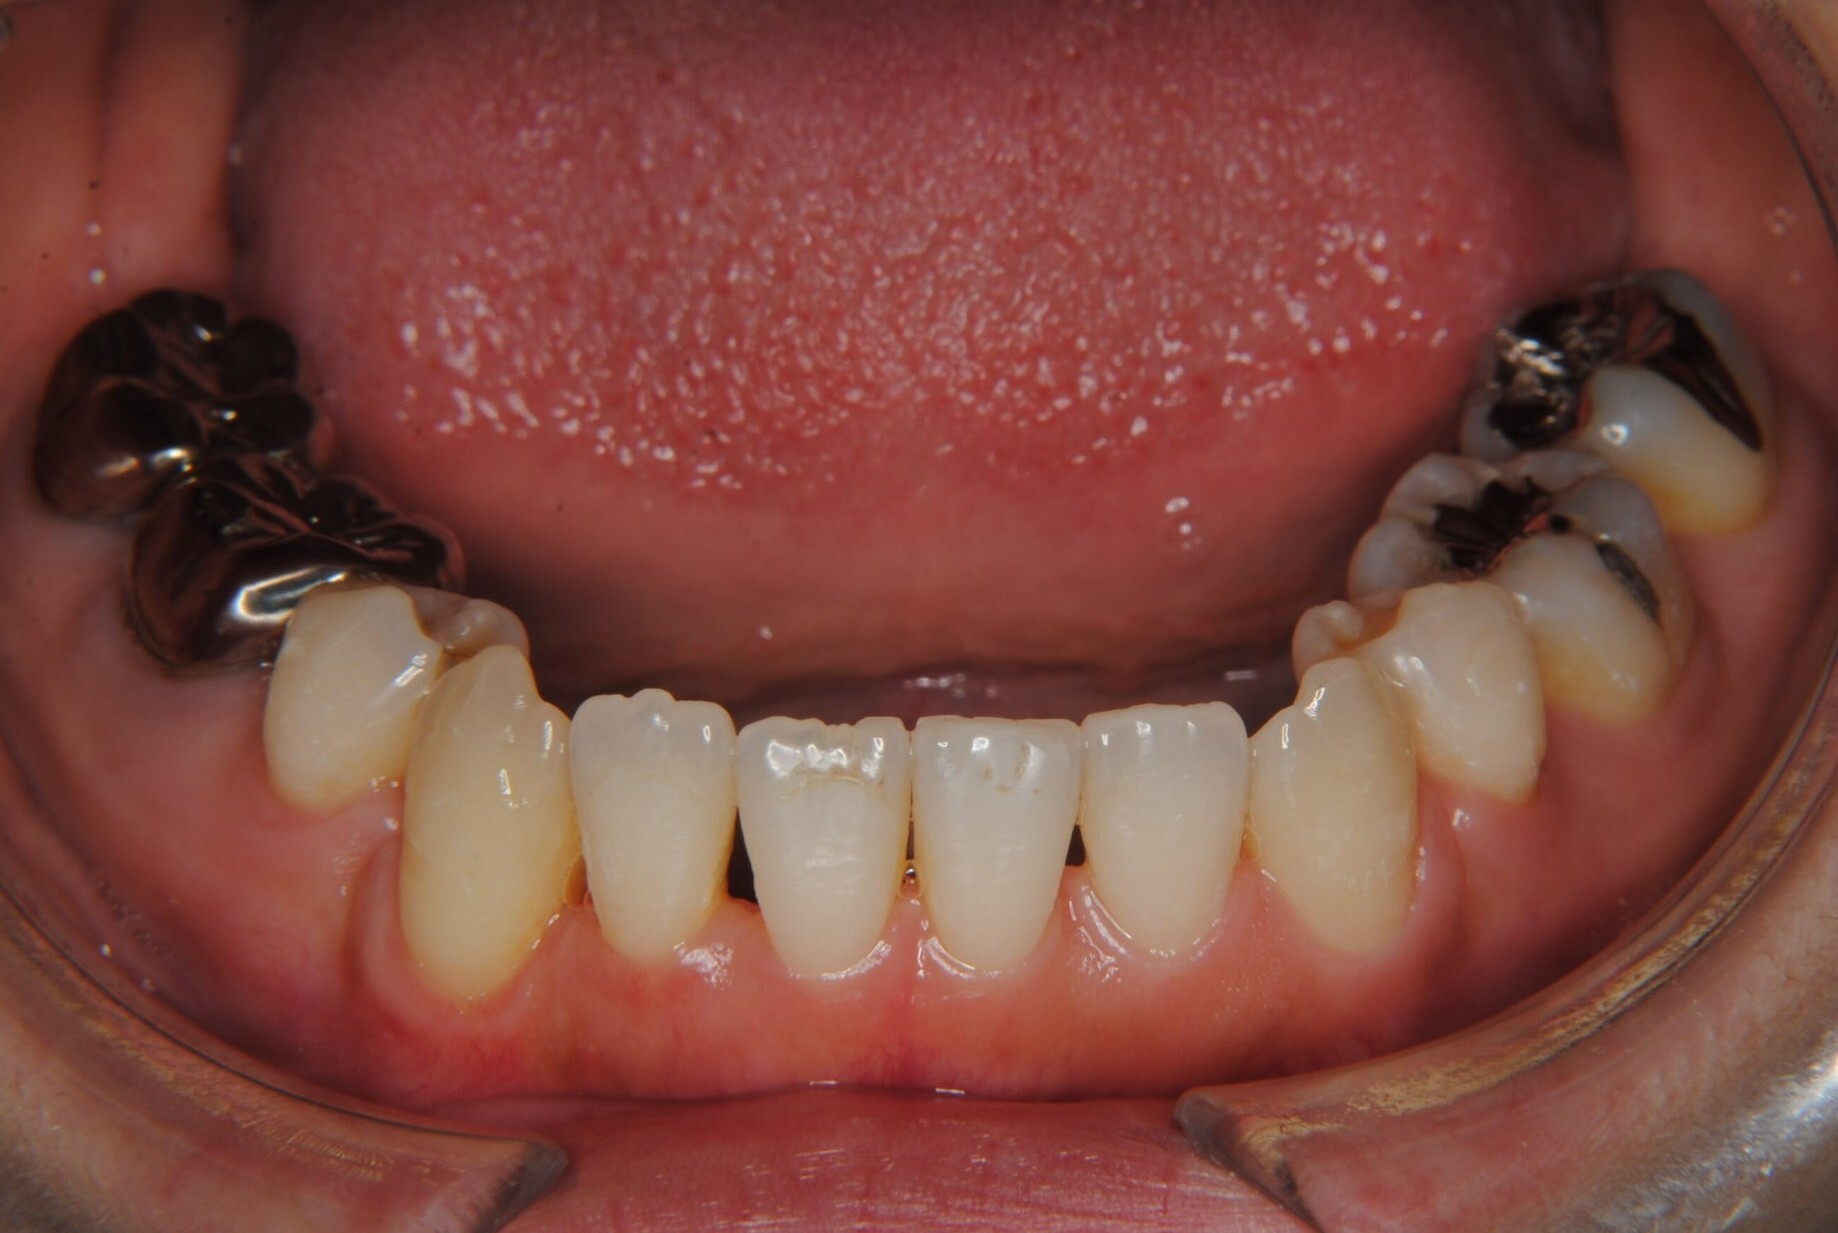

①主訴:八重歯、前歯のガタガタ、真ん中の不一致を治したい

②診断名:AngleⅠ級叢生

④治療に用いた主な装置:マルチブラケット装置(T21ブラケット)

⑤抜歯部位:上下左右第一小臼歯